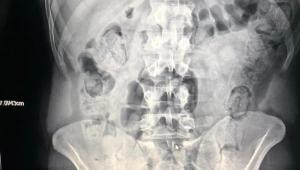

Kocaeli İl Emniyet Müdürlüğüne bağlı Narkotik Büro Ekipleri, almış oldukları duyum ve yaptıkları istihbarı çalışmalar sonucu, bazı şahısların Kocaeli üzerinden yüklü miktarda uyuşturucu sevkiyatı yapacağına dair bilgilere ulaştı. Şahısları bindikleri yolcu otobüsünde takibe alan ekipler, TEM Otoyolu üzeri İzmit İlçesinde durdurdu. Şahısların yapılan üst aramasındaki şüpheli hareketleri ve bir şüpheliye ait cekette üzerinde dışkı kalıntısı bulunan 25 fişek metamfetamin ele geçirilmesi üzerine ekipler durumdan şüphelendi. İran uyruklu olan 3 kişi gözaltına alınarak, savcılıktan alınan izin ile hastaneye götürüldü. Gözaltına alınan şüphelilerin çekilen röntgenlerinde midelerinde çok sayıda cisim olduğu görüldü. Bunun üzerine hekim kontrolünde şüphelilere verilen ilaçlar ile yabancı cisimleri çıkarmaları sağlandı. Toplamda 103 fişek halinde 871 gram metamfetamin ele geçirilen şüpheliler ifadelerinin alınmaları için Kocaeli İl Emniyet Müdürlüğüne götürüldü. Polise yakalanmamak amacıyla uyuşturucuları yutan şüphelilerin tamamlanan işlemleri sonrası Kocaeli Adliyesine sevk edilmesi bekleniyor.